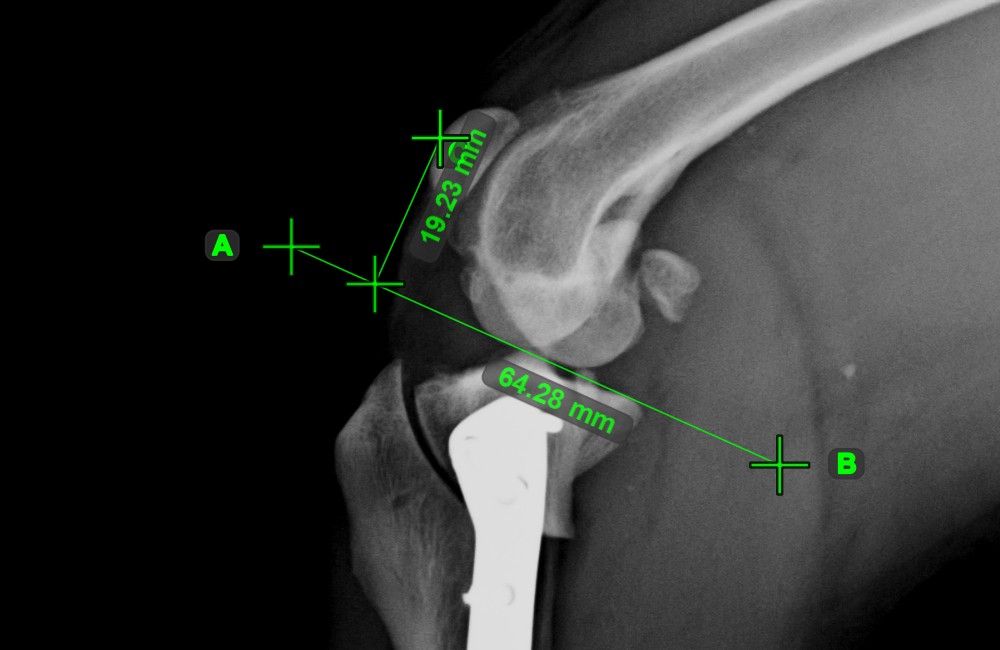

Line Measurement¶

Select the Line Measurement tool and assign it to one of the available mouse buttons. Place the start and end points on the scene or select them from already existing points on the image. The distance between the two points will be automatically

calculated by using the default calibration data, or the recalibrated data by the length calibration measurement.

Modify the start and end point by using the Select/Move Item tool. The distance between the two points will be automatically recalculated.